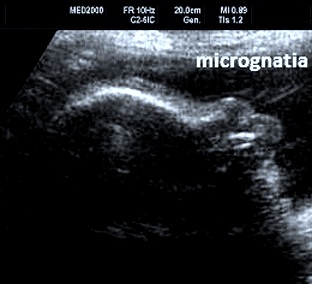

Così definita per le anomalie posturali e le contratture degli arti è una patologia generalizzata della cartilagine caratterizzata da distruzione della matrice cartilaginea, conseguente fibrosi e successiva ossificazione.

DIAGNOSI DIFFERENZIALE: si pone con l'artrogriposi dalla quale è facilmente riconoscibile per gli arti corti, il pollice da autostoppista ed i difetti del padiglione auricolare. Rispetto ad altre displasie scheletriche considerare che nelle displasia diastrofica le testa è sempre normale.